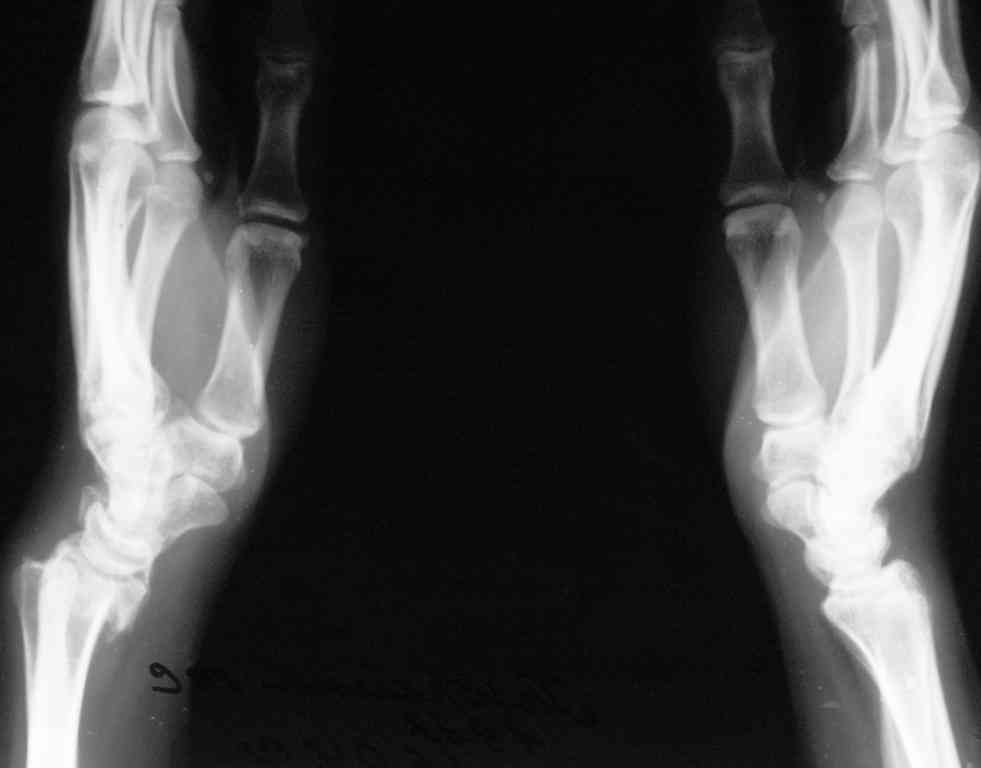

Судя по показанным Рг граммам, очевиден посттравм. артроз лучезапястного сустава, проблема дистального радиоульнарного сочленения(TFCC).

Первым этапом я бы убрал пластину с последующей ограниченной резекцией головки локтевой кости(hemiresection and interposition arthroplasty Bowers technique). провести курс реабилитации. если уровень мобильности сустава не

будет устраивать больного, можно рассмотреть проксимальную карпальную резекцию в качестве последующего этапа.

При наличии пронационной контрактуры (которая скорее всего и доминирует в его жалобах) и несращения локтевой кости в таком месте, операция Суав-Капанджи напрашивается сама собой.

Как вам видится такой вариант: убрать пластину с локтевой кости, выполнить резекцию локтевой вместе с псевдоартрозом, установить протез лучезапястного сустава?